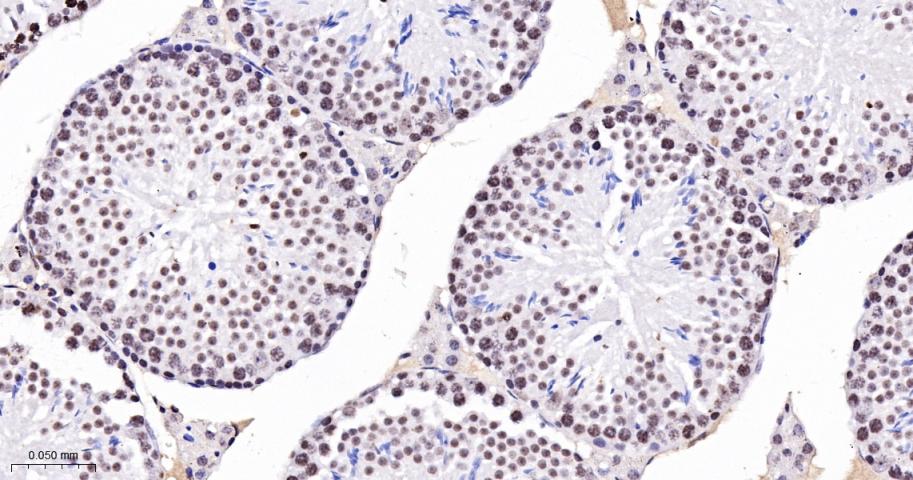

Paraformaldehyde-fixed, paraffin embedded Human Testicles; Antigen retrieval by boiling in sodium citrate buffer (pH6.0) for 15 min; The section was incubated with CDK8 Monoclonal Antibody, Unconjugated (bsm-60609R) at 1:100 overnight at 4°C, followed by conjugation to the bs-0295G-HRP and DAB (C-0010) staining.

Paraformaldehyde-fixed, paraffin embedded Rat Testicles; Antigen retrieval by boiling in sodium citrate buffer (pH6.0) for 15 min; The section was incubated with CDK8 Monoclonal Antibody, Unconjugated (bsm-60609R) at 1:100 overnight at 4°C, followed by conjugation to the bs-0295G-HRP and DAB (C-0010) staining.

Paraformaldehyde-fixed, paraffin embedded Mouse Testicles; Antigen retrieval by boiling in sodium citrate buffer (pH6.0) for 15 min; The section was incubated with CDK8 Monoclonal Antibody, Unconjugated (bsm-60609R) at 1:100 overnight at 4°C, followed by conjugation to the bs-0295G-HRP and DAB (C-0010) staining.